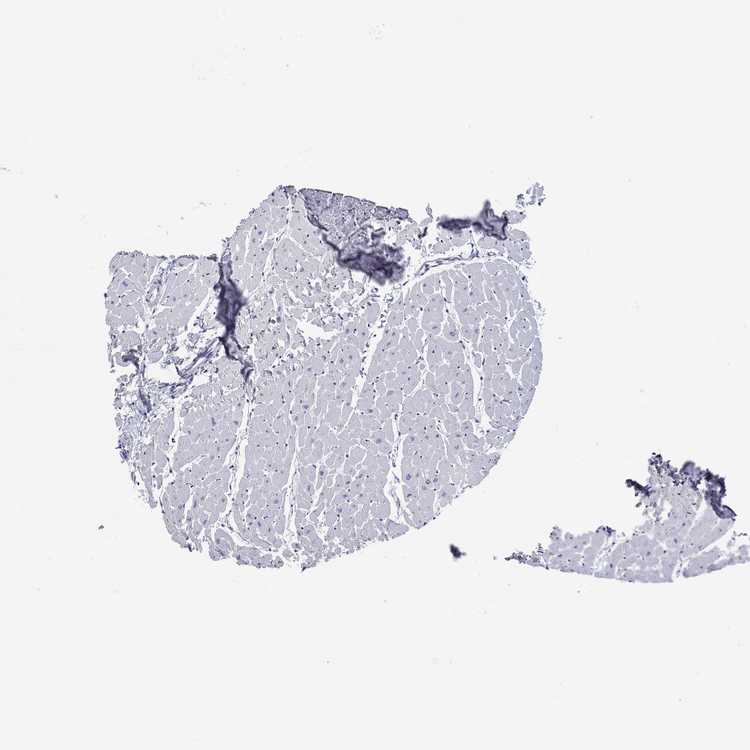

HEART MUSCLE - Antibody stainingi

Antibody staining in the annotated cell types in the current human tissue is reported as not detected, low, medium, or high, based on conventional immunohistochemistry profiling in selected tissues. This score is based on the combination of the staining intensity and fraction of stained cells.

Each image is clickable and will lead to virtual microscopy that enables deeper exploration of all samples and also displays staining intensity scores, fraction scores and subcellular localization as well as patient and tissue information for each sample.

Antibody HPA042294

Cardiomyocytes Medium